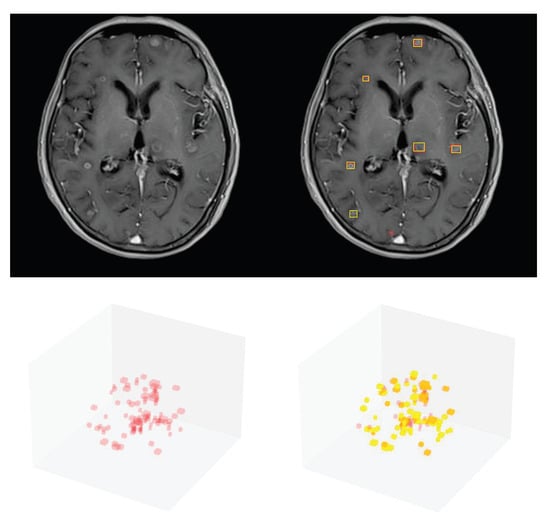

2.8. Postprocessing

3.1. Detection Performance of SA-YOLOv5

3.4. Detection Performance on the External Testing Set